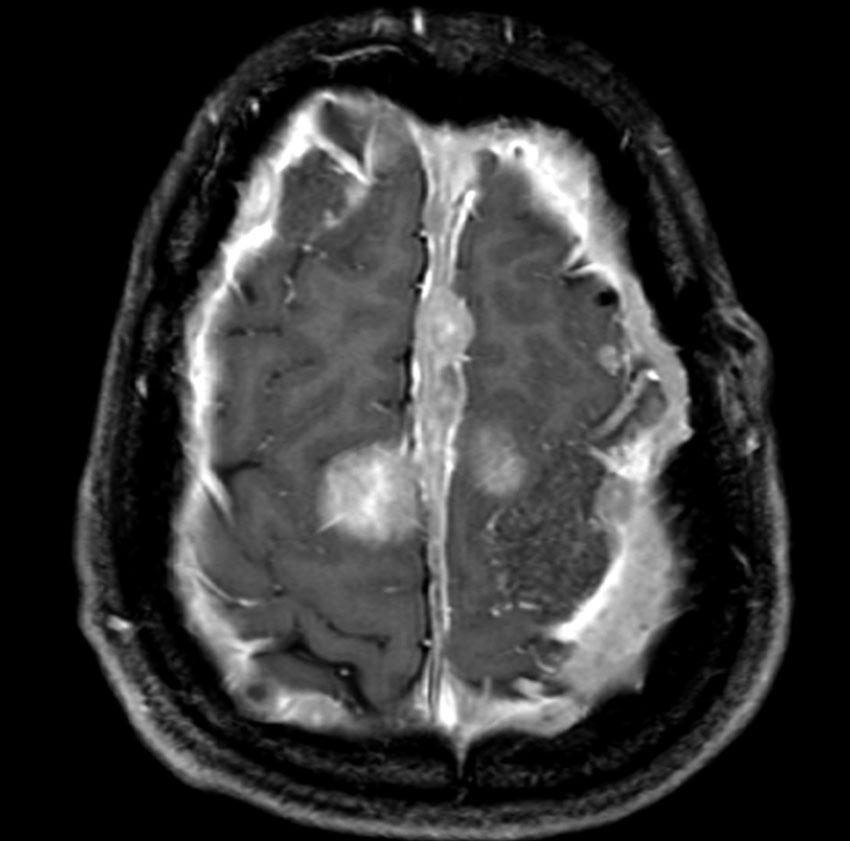

NF-2の多発性髄膜腫

赤の矢印が,両側の聴神経腫瘍です。黄色の矢印は, 多発性の髄膜腫です。蝶形骨縁髄膜腫,穹隆部髄膜腫,大脳鎌髄膜腫,大脳鎌テント接合部髄膜腫などいっぱいあります。これらは基本的に経過観察しますが,とても目立って大きくなるものがあれば摘出します。摘出には注意が必要で,近い将来また手術になるかもしれないので,次回の手術もできるように工夫して開頭手術しなければなりません。でないと,次の手術での合併症が増えます。また一回の開頭で近傍の硬膜や腫瘍を可能な限り摘出してしまうことも大切です。でないと,限りなく手術を繰り返すことになります。